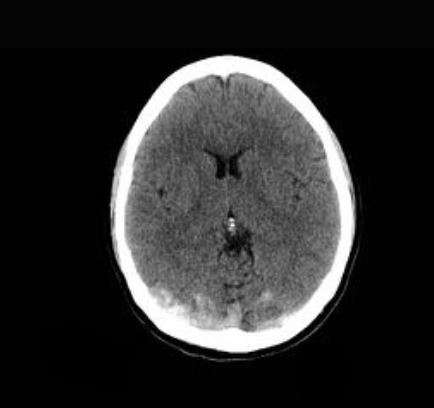

El diagnóstico de la trombosis venosa intracraneal es un proceso crítico que requiere el uso de técnicas de imagen avanzadas para identificar la presencia de coágulos en los senos venosos del cerebro y evaluar el impacto de estos en la hemodinámica cerebral. Entre las modalidades de imagen más empleadas se encuentran la tomografía computarizada y la resonancia magnética venosa, cada una con sus ventajas y limitaciones.

La tomografía computarizada es un método rápido y ampliamente disponible que permite la evaluación inicial en casos de sospecha de trombosis venosa intracraneal. Esta técnica utiliza rayos X para crear imágenes transversales detalladas del cerebro, lo que facilita la identificación de cambios agudos en la densidad del tejido cerebral, como hemorragias o infartos. En algunos casos, la tomografía computarizada puede incluir la administración de contraste para mejorar la visualización de los vasos sanguíneos, lo que ayuda a detectar la oclusión del seno venoso. Sin embargo, es importante tener en cuenta que, aunque la tomografía computarizada puede revelar ciertos signos indirectos de trombosis, como la expansión del seno venoso o la presencia de edema cerebral, puede no ser tan sensible como la resonancia magnética para detectar trombosis en fases iniciales.